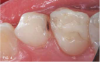

Case 3. This 10-year-old boy was brought to the office for a second opinion regarding restoration of the left primary first molar, which was causing sensitivity (Figure 8). The boy's mother reported that a "tooth-colored filling" had been suggested at another office. The boy was terrified of needle injections and, according to his mother, had required sedation in prior years for restoration of maxillary primary molars. SDF was applied (Figure 9), tooth sensitivity was eliminated, and in 3 months, clinical evaluation and a periapical radiograph confirmed that no other treatment would be needed until the tooth exfoliated (Figure 10 and Figure 11).

Fig 8. 10-year-old patient with distal caries lesion of primary  rst molar. (

Fig 8

Fig 9. SDF applied.

Fig 9

Fig 10. 3 months after SDF application, no additional treatment needed.

Fig 10

Fig 11. 3 months after SDF application, no additional treatment needed.

Fig 11